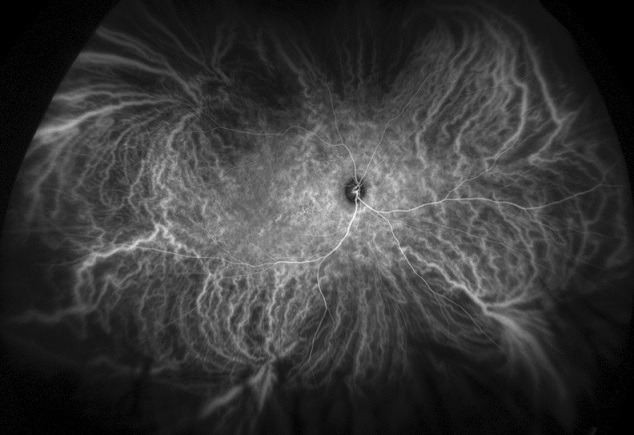

The scanning laser includes Indocyanine Green Angiography (ICG) ultra-widefield, ultra-high resolution angiography, enabling a simultaneous pole-to-periphery view of the retina. This allows the entire retinal vasculature to be imaged during the dye transit by a non-contact method. This supports practitioners in diagnosing ocular pathology that may first present in the periphery of the retina, resulting in better patient outcomes.